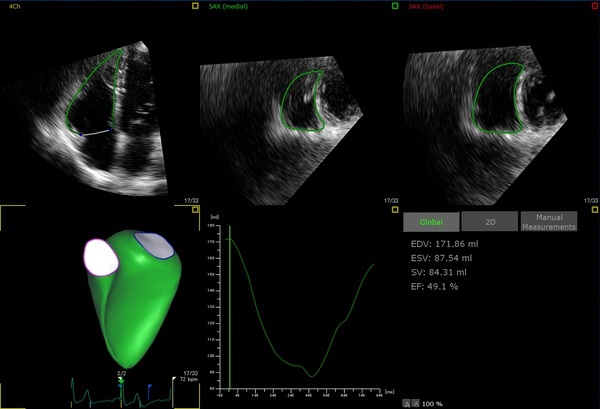

Dynamic HeartModel

取得した心臓3Dデータから、自動で心臓の駆出率(EF)を算出し、手動での計測と比較して最大82%の時間短縮を実現します。